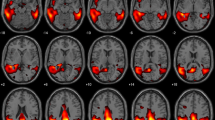

Selection of HC images was based on visual rating, after Cook’s distance and jack-knife analyses, to exclude artefacts and/or outliers. The performance of these HC datasets (ADNI-HC and AIMN-HC) to extract hypometabolism patterns in single patients was tested in comparison with the standard reference HC dataset (HSR-HC) by means of Dice score analysis. We evaluated the performance and comparability of the different HC datasets in the assessment of single-subject SPM-based hypometabolism in three independent cohorts of patients, namely, ADD, bvFTD and DLB.

Two-step Cook’s distance analysis and the subsequent jack-knife analysis resulted in the selection of n = 125 subjects from the AIMN-HC dataset and n = 75 subjects from the ADNI-HC dataset. The average concordance between SPM hypometabolism t-maps in the three patient cohorts, as obtained with the new datasets and compared to the HSR-HC standard reference dataset, was 0.87 for the AIMN-HC dataset and 0.83 for the ADNI-HC dataset. Pattern expression analysis revealed high overall accuracy (> 80%) of the SPM t-map classification according to different statistical thresholds and sample sizes.